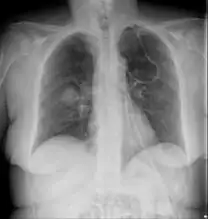

Imaging

Imaging is often performed, such as CT scan of lungs and sinuses.[38] Signs on chest CT scans, such as nodules, cavities, halo signs, pleural effusion and wedge-shaped shadows, showing invasion of blood vessels may suggest a fungal infection, but does not confirm mucormycosis.[16] A reverse halo sign in a person with a blood cancer and low neutrophil count, is highly suggestive of mucormycosis.[16] CT scan images of mucormycosis can be useful to distinguish mucormycosis of the orbit and cellulitis of the orbit, but imaging may look identical to those of aspergillosis.[16] MRI may also be useful.[39]

Chest X-ray: likely fungal infection left lung in an immunocompromised person